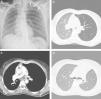

a) Chest radiograph showing a left side pneumothorax (arrows). b) Chest CT showing increased left lung volume with contralateral mediastinum shift and decreased ipsilateral lung attenuation. c) Chest CT showing a 2 cm lesion in the left main bronchus. d) Chest CT, eighteen moths after surgery, showing resolution of the mediastinum shift and similar bilateral lung attenuations.

We report the case of a 30‐year‐old woman who presented to the emergency department of our hospital center with complaints of a recent left side pleuritic chest pain and a history of cough over the past 2 months. She was a non‐smoker. Physical examination and chest radiograph indicated a left side pneumothorax (Fig. 1a). An intercostal tube was inserted; the lung fully expanded without any detectable air‐leak and the chest tube was removed. At discharge the patient was asymptomatic and chest radiograph showed no abnormalities. Two months later she returned with new onset hemoptysis. Chest radiograph showed a small left side pneumothorax and increased ipsilateral lung volume with a contralateral mediastinum shift, both of which increased with expiration. A chest computed tomography (CT) confirmed these alterations with significantly decreased ipsilateral lung attenuation and showed a 2cm lesion in the left main bronchus (Fig. 1b and c). Bronchoscopy showed a cherry red polypoid tumor, easily hemorrhagic, causing an almost total obstruction of the left main bronchus. Biopsy of the tumor indicated a typical carcinoid tumor. An octreotide scan revealed uptake solely in the lesion of the left main bronchus and so a sleeve‐type surgery was performed with excision of the main bronchus and lobectomy of left upper lobe. Histological examination confirmed a typical carcinoid tumor of the left main bronchus and showed no signs of emphysema or pleural blebs. The post‐surgical period was insignificant and the patient was discharged home. Eighteen months after surgery she is asymptomatic, had no new pneumothoraces and her chest CT shows resolution of the mediastinum shift and similar bilateral lung attenuations (Fig. 1d).